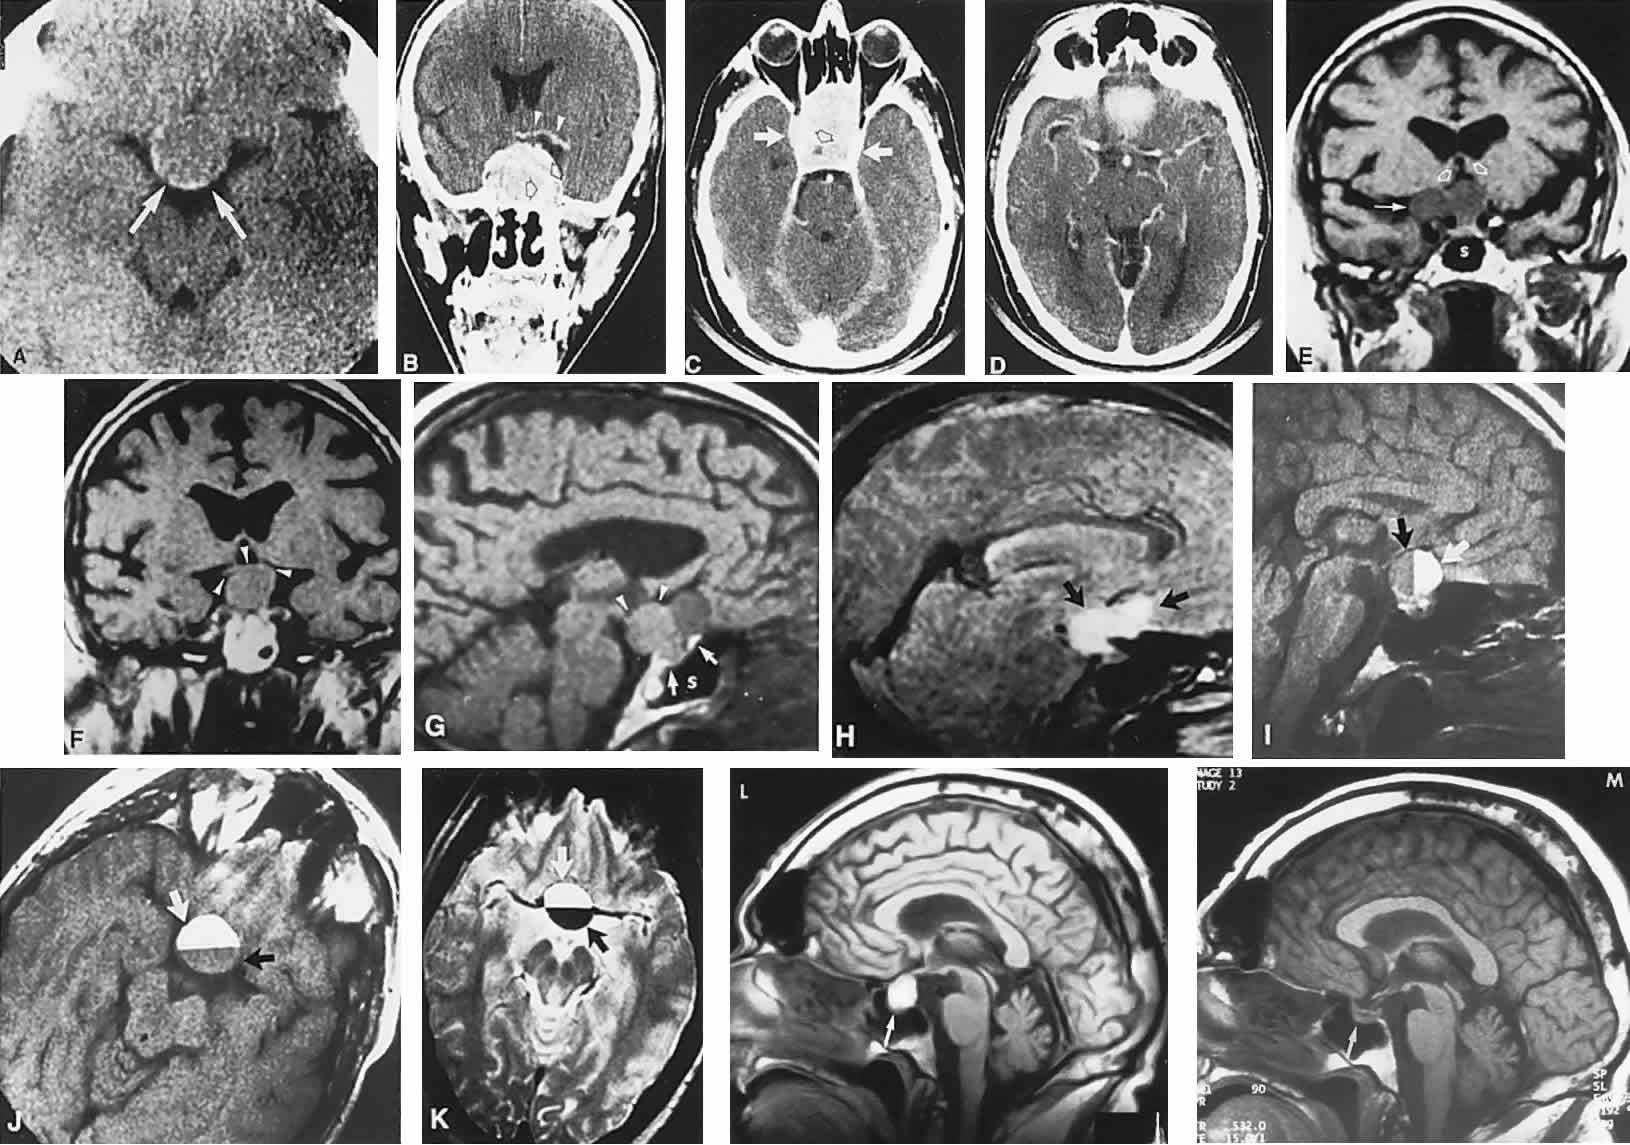

report. J Neurosurg 68:300, 1988 95. Cushing HW: Papers Relating to the Pituitary Body, Hypothalamus, and Parasympathetic

site, and treatment. J Neurosurg 68:85, 1988 102. Hoyt WF, Baghdassarian SA: Optic glioma of childhood: natural history and rationale for conservative

management. Br J Ophthalmol 53:793, 1969 103. Blatt J, Jaffe R, Deutsch M et al: Neurofibromatosis and childhood tumors. Cancer 57:1225, 1986 104. Lewis RA, Gerson LP, Axelson KA et al: Von Recklinghausen neurofibromatosis. II. Incidence of optic gliomata. Ophthalmology 91:929, 1984 105. Bognanno JR, Edwards MK, Lee TA et al: Cranial MR imaging in neurofibromatosis. AJNR Am J Neuroradiol 9:461, 1988 106. Miller NR, Iliff WJ, Green WR: Evaluation and management of gliomas of the anterior visual pathways. Brain 97:743, 1974 107. McCullough DC, Epstein F: Optic pathway tumors: a review with proposals for clinical staging. Cancer 56:1789, 1985 108. Layden WE, Edwards WC: Ocular manifestations of the dien-cephalic syndrome. Am J Ophthalmol 73:78, 1972 109. Arnoldi KA, Tychsen L: Prevalence of intracranial lesions in children originally diagnosed with

disconjugate nystagmus (spasmus nutans). J Pediatr Ophthalmol Stabismus 32:296, 1995 110. DeSousa AC, Kalsbeck JE, Mealey J, Fitzgerald J: Diencephalic syndrome and its relation to optico-chiasmatic glioma: review

of twelve cases. Neurosurgery 4:207, 1979 111. Poussaint TY, Barnes PD, Nichols K et al: Diencephalic syndrome: clinical features and imaging findings. AJNR Am J Neuroradiol 18:1499, 1997 112. Perlongo G, Carollo C, Salviati L et al: Diencephalic syndrome and disseminated juvenile pilocytic astrocytomas

of the hypothalamic-optic chiasm region. Cancer 80:142, 1997 113. Rieth KG, Comite F, Dwyer AJ et al: CT of cerebral abnormali-ties in precocious puberty. AJR Am J Roentgenol 148:1231, 1987 114. Bronen RA, Fulbright RK, Reynders CS et al: Magnetic resonance imaging of central precocious puberty: the importance

of hypothalamic abnormalities. Int J Neuroradiol 1:145, 1995 115. Habiby R, Silverman B, Listernick R et al: Precocious puberty in children with neurofibromatosis type 1. J Pediatr 126:364, 1995 116. Lavery MA, O'Neill JF, Chu FC et al: Acquired nystagmus in early childhood: a presenting sign of intracranial

tumor. Ophthalmology 91:425, 1984 117. Glaser JS, Hoyt WF, Corbett J: Visual morbidity with chiasmal glioma: long-term studies of visual fields

in untreated and irradiated cases. Arch Ophthalmol 85:3, 1971 118. Fletcher WA, Imes RK, Hoyt WF: Chiasmal gliomas: appearance and long-term changes demonstrated by computerized

tomography. J Neurosurg 65:154, 1986 119. Lourie GL, Osborne DR, Kirks DR: Involvement of posterior visual pathways by optic nerve gliomas. Pediatr Radiol 16:271, 1986 120. Patronas NJ, Dwyer AJ, Papathanasiou M et al: Contributions of magnetic resonance imaging in the evaluation of optic

gliomas. Surg Neurol 28:367, 1987 121. Menor F, Marti-Bonmati L: CT detection of basal ganglion lesions in neurofibromatosis type 1: correlation

with MRI. Neuro-radiology 34:305, 1992 122. Albright AL, Sclabassi RJ: Use of the Cavitron ultrasonic aspirator (CUSA) and visual evoked potentials

for chiasmal gliomas of children. J Neurosurg 63:138, 1985 123. Coppeto JR, Monteiro ML, Uphoff DF: Exophytic suprasellar gliomas: a rare cause of chiasmatic compression. Case

report. Arch Ophthalmol 105:28, 1987 124. Massry GG, Morgan CF, Chung SM: Evidence of optic pathway gliomas after previously negative neuroimaging. Ophthalmology 104:930, 1997 125. Parazzini C, Triulzl F, Bianchini E et al: Spontaneous involution of optic pathway lesions in neurofibromatosis type 1: serial

contrast MR evaluation. AJNR Am J Neuroradiol 16:1711, 1995 126. Leisti EL, Pyhtinen J, Poyhonen M: Spontaneous decrease of a pilocytic astrocytoma in neurofibromatosis type 1. AJNR Am J Neuroradiol 17:1691, 1996 127. Imes RK, Hoyt WF: Childhood chiasmal gliomas: update on the fate of patients in the 1969 San

Francisco study. Br J Ophthalmol 70:179, 1986 128. Pierce SM, Barnes PD, Loeffler JS et al: Definitive radiation therapy in the management of symptomatic patients

with optic glioma: survival and long-term effects. Cancer 65: 45, 1990 129. Kovalic JJ, Grigsby PW, Shepard MJ et al: Radiation therapy for gliomas of the optic nerve and chiasm. Int J Radiat Oncol Biol Phys 18:927, 1990 130. Tao ML, Barnes PD, Billet AL et al: Childhood optic chiasm gliomas: radiographic response following radiotherapy

and long-term clinical outcome. Int J Radiat Oncol Biol Phys 39:579, 1997 131. Erkal HS, Serin M, Cakmak A: Management of optic pathway and chiasmatic-hypothalmic gliomas in children

with radiation therapy. Radiother Oncol 45:11, 1997 132. Danoff BF, Cowchock FS, Marquette C et al: Assessment of the long-term effects of primary radiation therapy for brain

tumors in children. Cancer 49:1580, 1982 133. Packer RJ, Savino PJ, Bilaniuk LT et al: Chiasmatic gliomas of childhood: a reappraisal of the natural history and

effectiveness of cranial irradiation. Childs Brain 10:393, 1983 134. Davis PC, Hoffman JC, Pearl GS et al: CT evaluation of effects of cranial radiation therapy in children. AJNR Am J Neuroradiol 7:639, 1986 135. Beyer RA, Paden P, Sobel DF et al: Moyamoya pattern of vascular occlusion after radiotherapy for gliomas of

the optic chiasm. Neurology 36:1173, 1986 136. Packer RJ, Ater J, Allen J et al: Carboplatin and vincristine chemotherapy for children with newly diagnosed

progressive low-grade gliomas. J Neurosurg 86:747, 1997 137. Chamberlain MC: Recurrent chiasmatic-hypothalamic glioma treated with oral etoposide. Arch Neurol 52:509, 1995 138. Safneck JR, Napier LB, Halliday WC: Malignant astrocytoma of the optic nerve in a child. Can J Neurol Sci 19:498, 1992 139. Aroichane M, Miller NR, Eggenberger ER: Glioblastoma multiforme masquerading as pseudotumor cerebri: case report. J Clin Neuroophthalmol 13:105, 1993 140. Hoyt WF, Meshel LG, Lessell S et al: Malignant optic glioma of adulthood. Brain 96:121, 1973 141. Taphoorn MJB, de Vries-Knoppert WAEJ, Ponssen H et al: Malignant optic glioma in adults. J Neurosurg 70:277, 1989 142. Millar WS, Tartaglino LM, Sergott RC et al: MR of malignant optic glioma of adulthood. AJNR Am J Neuroradiol 16:1673, 1995 143. Albers GW, Hoyt WF, Forno LS et al: Treatment response in malignant optic glioma of adulthood. Neurology 38: 1071, 1988 144. Matsutani M, Sano K, Takakura K et al: Primary intracranial germ cell tumors: a clinical analysis of 153 histologically

verified cases. J Neurosurg 86:446, 1997 145. Camins MB, Mount LA: Primary suprasellar atypical teratoma. Brain 97:447, 1974 146. Wilson JT, Wald SL, Aitken PA et al: Primary diffuse chiasmatic germinomas: differentiation from optic chiasm

gliomas. Pediatr Neurosurg 23:1, 1995 147. Lumsden CE: The neuropathology of multiple sclerosis. In Vinken PJ, Bruyn